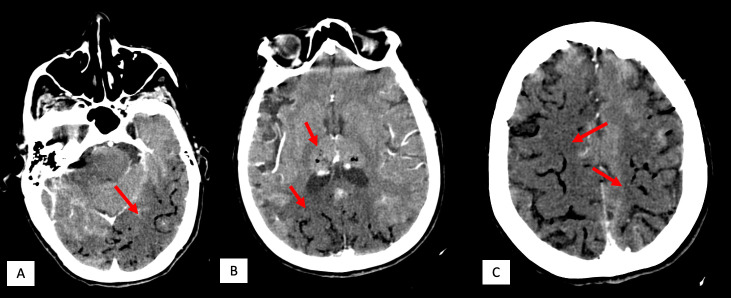

Clinical case: 76-year-old patient with pre-existing diffuse interstitial lung disease, who experienced a massive stroke due to spontaneous pneumomediastinum. Her presentation included confusion, seizures, and motor weakness. Imaging tests revealed air bubbles in the cerebral sulci and hypodense areas in the cerebellum and parietooccipitals. In addition, pneumothorax and air in the upper mediastinum were noted on chest radiographs and chest CT scan. Despite therapeutic measures such as hyperbaric oxygen, the patient unfortunately died due to multiple organ failure.